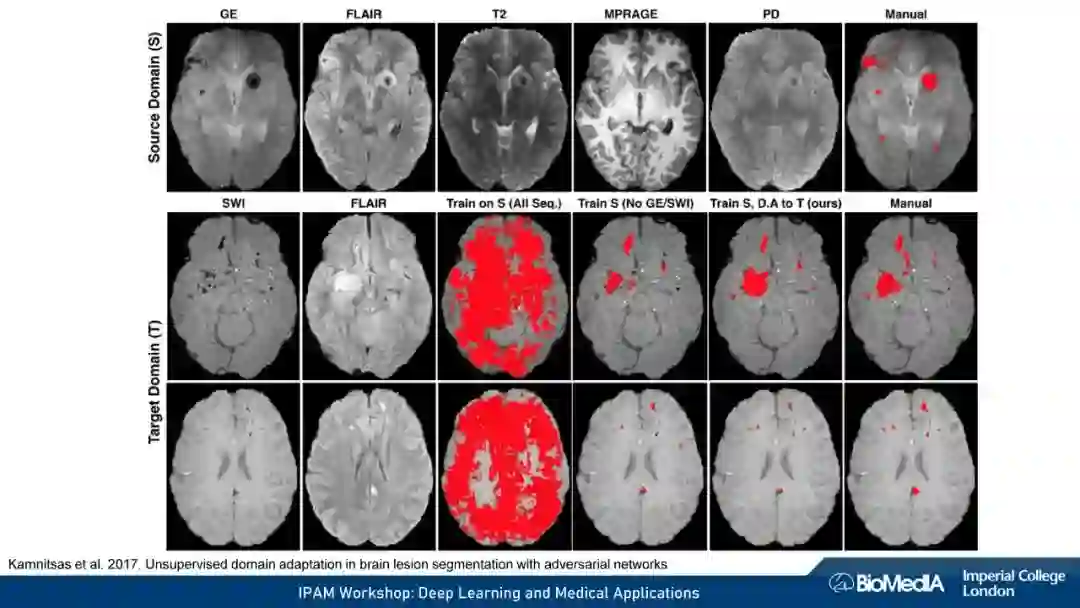

我们使用因果推理来阐明医学成像的关键挑战:1) 数据稀缺,即高质量注释的有限可用性 2) 数据不匹配,即训练有素的算法可能无法在临床实践中推广。我们认为,图像、注释和数据收集过程之间的因果关系不仅会对预测模型的性能产生深远的影响,甚至可能决定首先应该考虑哪种学习策略。例如,半监督可能不适合于图像分割——这可能是我们在医学图像分析中因果关系考虑的一个令人惊讶的见解。我们的结论是,对于基于机器学习的图像分析的成功至关重要的是,研究人员要能意识到并解释他们的数据背后的因果关系。